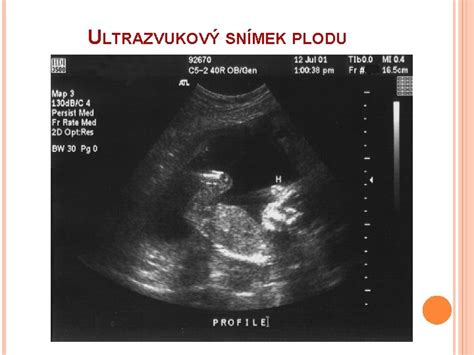

Vo 13. týždni tehotenstva by ste už mali mať za sebou prvú gynekologickú prehliadku a ultrazvukové vyšetrenie. Onedlho vás čaká odber krvi na AFP (alfa-fetoproteín) alebo tripple test. Tieto testy slúžia na zistenie zvýšeného rizika vrodených chýb dieťaťa v porovnaní s bežným rizikom pre váš vek. V prípade zistenia zvýšeného rizika (napríklad Downov syndróm) môže nasledovať presnejšie diagnostické vyšetrenie.

Dôležitým vyšetrením je tiež ultrazvukový screening medzi 11. a 13. týždňom tehotenstva, známy ako NT (Nuchal Translucency) screening alebo meranie šijového prejasnenia. Tento screening, ktorý môže vykonať len vyškolený sonografista s kvalitným ultrazvukom, umožňuje včasnú detekciu potenciálnych problémov na strane bábätka. Výsledky sú dostupné ihneď, čím sa predchádza dlhodobému stresu pre celú rodinu.